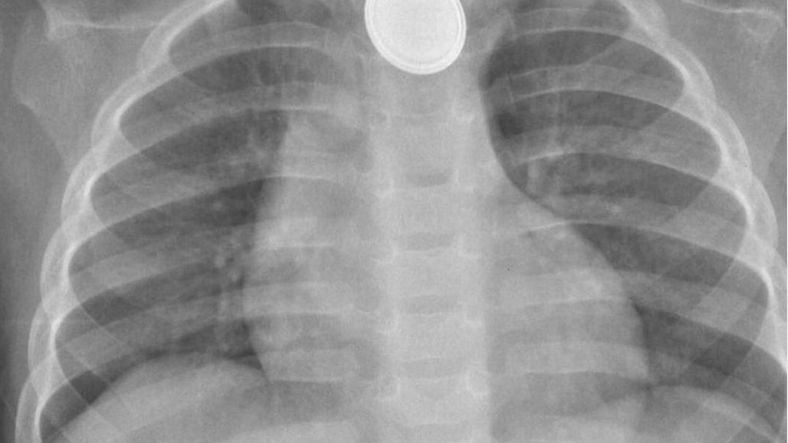

W szpitalu maluch przeszedł kompleksową diagnostykę. Dopiero badanie RTG potwierdziło, że Ralphie połknął baterię guzikową, która widoczna była na prześwietleniu klatki piersiowej.

Lekarze podjęli szybką decyzję o operacji. Zabieg trwał trzy godziny.